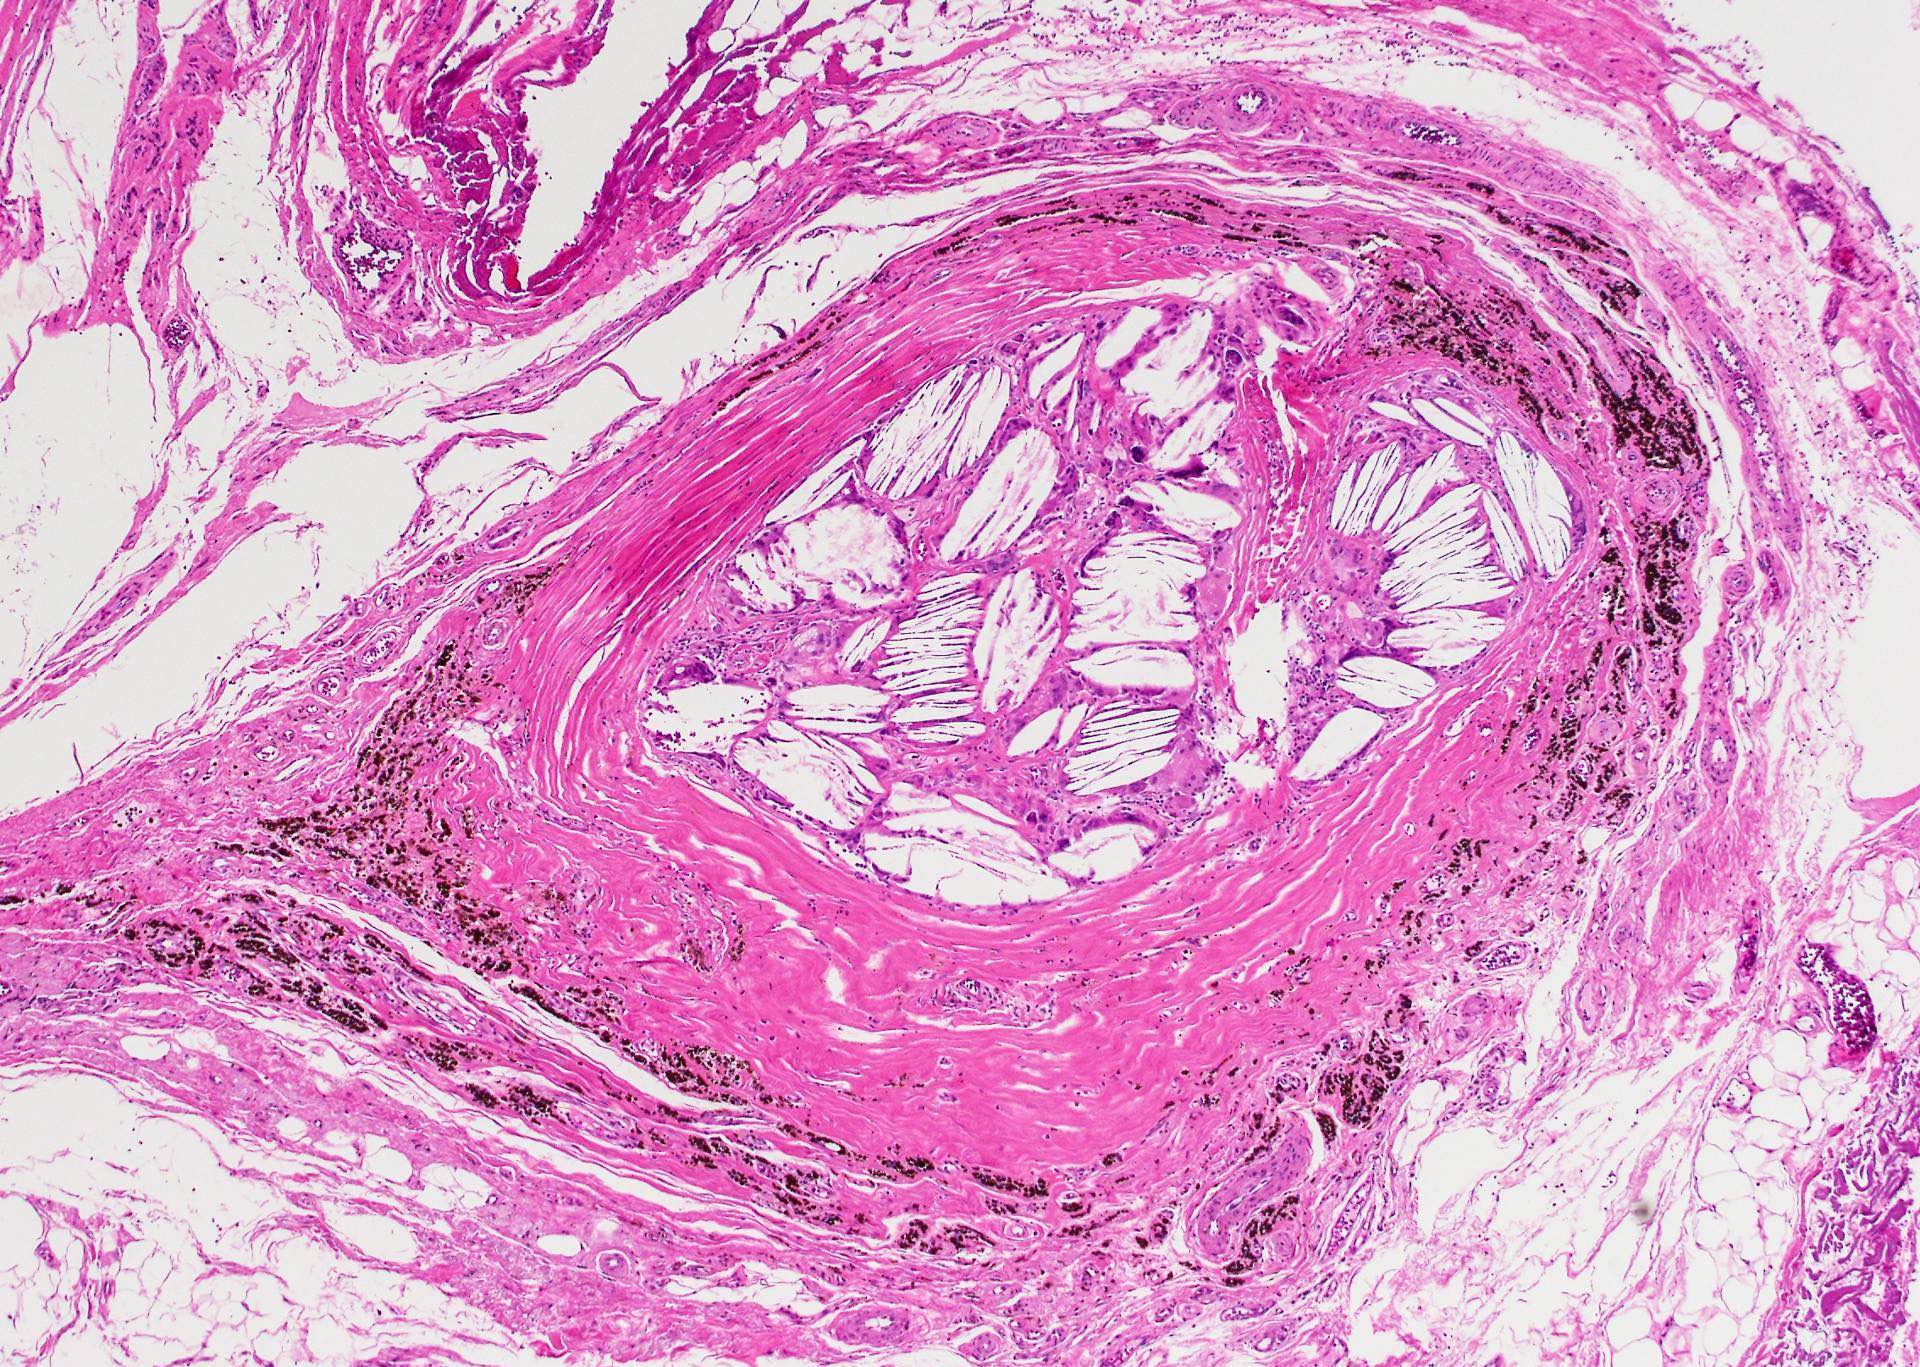

Microscopic (histologic) description

- Thyroid follicles in the cyst / duct wall:

- Found in 30% - 60%, with higher yield on serial sections

- More common in infra- versus suprahyoid remnants, on the right paramedian side (Ann Otol Rhinol Laryngol 2000;109:1135)

- Seen in small irregular groups

- Thyroid epithelium may be normal or rarely hyperplastic or neoplastic

- Thyroid tissue often hidden by inflammation (Laryngoscope 2001;111:1002)

- Absence of thyroid tissue does not exclude the diagnosis of TGD cyst

- Occasional inclusions:

- Skin adnexal structures (J Laryngol Otol 2004;118:996)

- Cartilage (Int J Pediatr Otorhinolaryngol 1988;15:205)

- Cholesterol granuloma (Eur Arch Otorhinolaryngol 2009;266:1775)

Microscopic (histologic) images

Contributed by Andrey Bychkov, M.D., Ph.D., Mark R. Wick, M.D. and AFIP